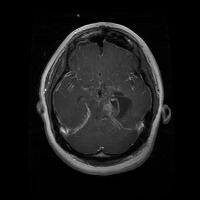

This project has created a labeled MRI brain tumor dataset for the detection of three tumor types: pituitary, meningioma, and glioma. The dataset contains 2443 total images, which have been split into training, validation, and test sets. The training set has 1695 images, the validation set has 502 images, and the test set has 246 images.

- Image types: MRI scans

Classes:

- Pituitary tumor

- Meningioma tumor

- Glioma tumor

- No Tumor

- The images have been labeled by medical experts using a standardized labeling protocol.

- The labels include the type of tumor and the location of the tumor.